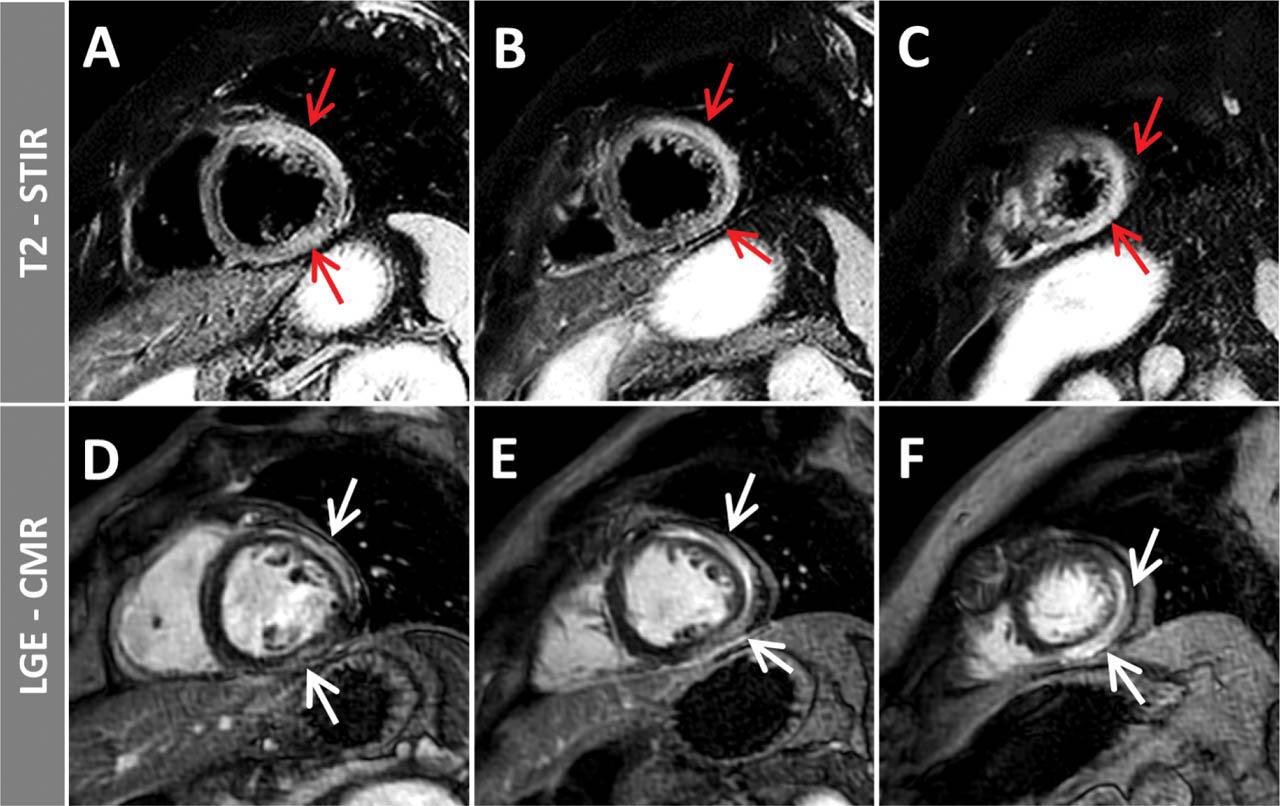

Figure 5

Edema sensitive T2-STIR (A, B, C) and LGE images (D, E, F) in a patient with acute viral myocarditis. Acute, non-ischemic, inflammatory changes with edema (T2-hyperintensity, red arrows) and LGE (white arrows) in the subepicardium of the inferior and lateral walls, extending towards the anterior wall, can be noticed.